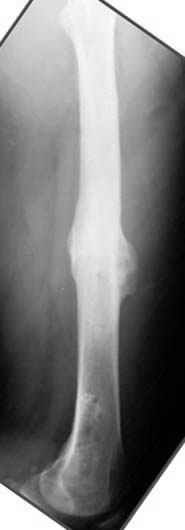

Несколько снимков из моей коллекции, чтобы разьяснить, почему мы до сих пор делаем различные варианты остеотомии.

На рисунке N1 предоперационный план лечения ложного сустава шейки бедра- линия ложного сустава, угол и направление введения импланта, клиновидная остеотомия в градусах и миллиметрах, второй снимок после коррекции, расчет, на сколько удлиняется конечность и размеры импланта;

N3 рисунок окончательный снимок, после операции моя рентгенограмма должен выглядеть примерно как эта картина. На N4 снимке клин перед удалением; N5 послеоперации 3 нед.; N6 окончательная рентгенограмма.

Отправитель: Djoldas Kuldjanov 23 Ноябрь 2004, 18:21

пластическая модель; и коррекция бедра аппаратом Илизарова.

Имею другие снимки тоже, получится как отчет о моей работе.

Узкий к-м канал - тонкий гвоздь- усталостный перелом дистальных винтов - развитие нестабильности и как ее результат остеолиз вокруг гвоздя - деформация анатомической оси бедра. Похоже, что я понял почему аппарат, а не новый гвоздь:-)